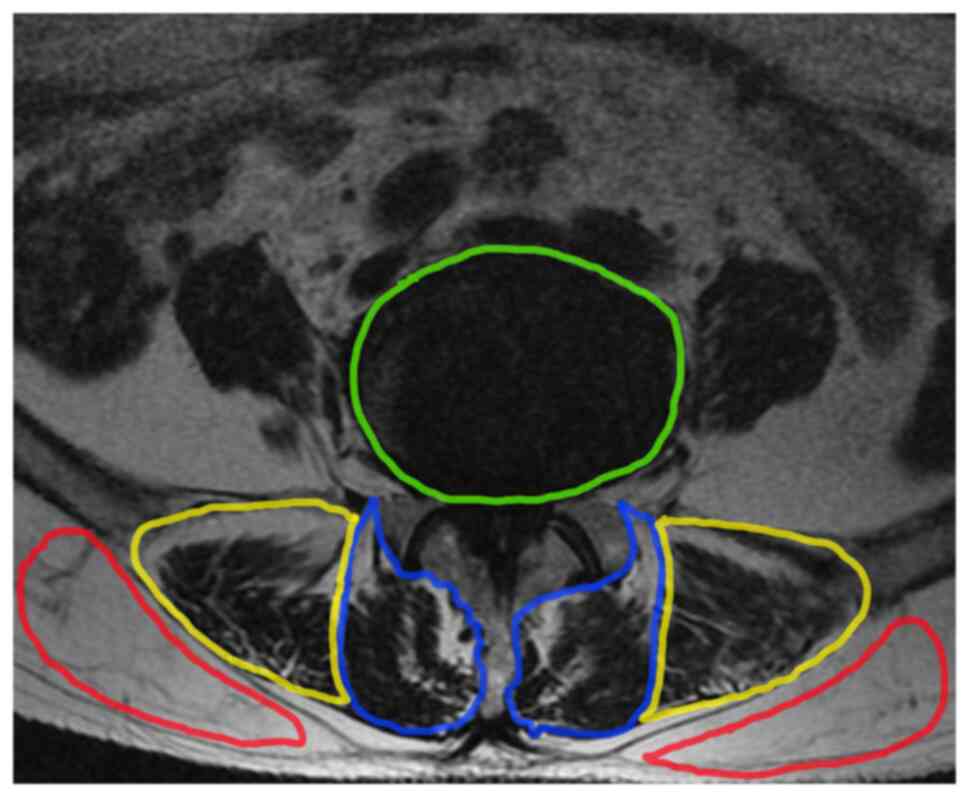

Figure 3

Example of the area of interest defined using ImageJ. Erector spinae CSA is indicated by yellow color, CSA of the target vertebral body is indicated by green, multifidus-CSA by blue and subcutaneous fat range by red. CSA, cross-sectional area.

After image selection, a region of interest was drawn using ImageJ (v1.53c; National Institutes of Health) (Fig. 3), and the bilateral paravertebral muscles cross-sectional area (CSA) of the upper vertebral body at the lesion space, and subcutaneous fat extent were demonstrated and analyzed. The relative CSA (RCSA) was calculated using the following formula: Paravertebral muscle area/vertebral body area x 100% (the interindividual difference mostly decreased using this ratio). Furthermore, the software threshold technique (15) was used to measure the gray values of paravertebral muscles and the subcutaneous fat (Fig. 4), which were subsequently imported into Microsoft® Excel for Mac (v.16.48; Microsoft Corporation) and line graphs were created for analysis (Fig. 5). The ratio of the gray values of the coincident parts of the two to the gray values of paravertebral muscles was used to calculate the fatty infiltration ratio (FIR) (16). It is important to note that if the areas of interest of the multifidus and erector spinalis muscles cannot be drawn on the lumbar MRI, the case will be excluded. All parameters were measured using an independent attending physician.